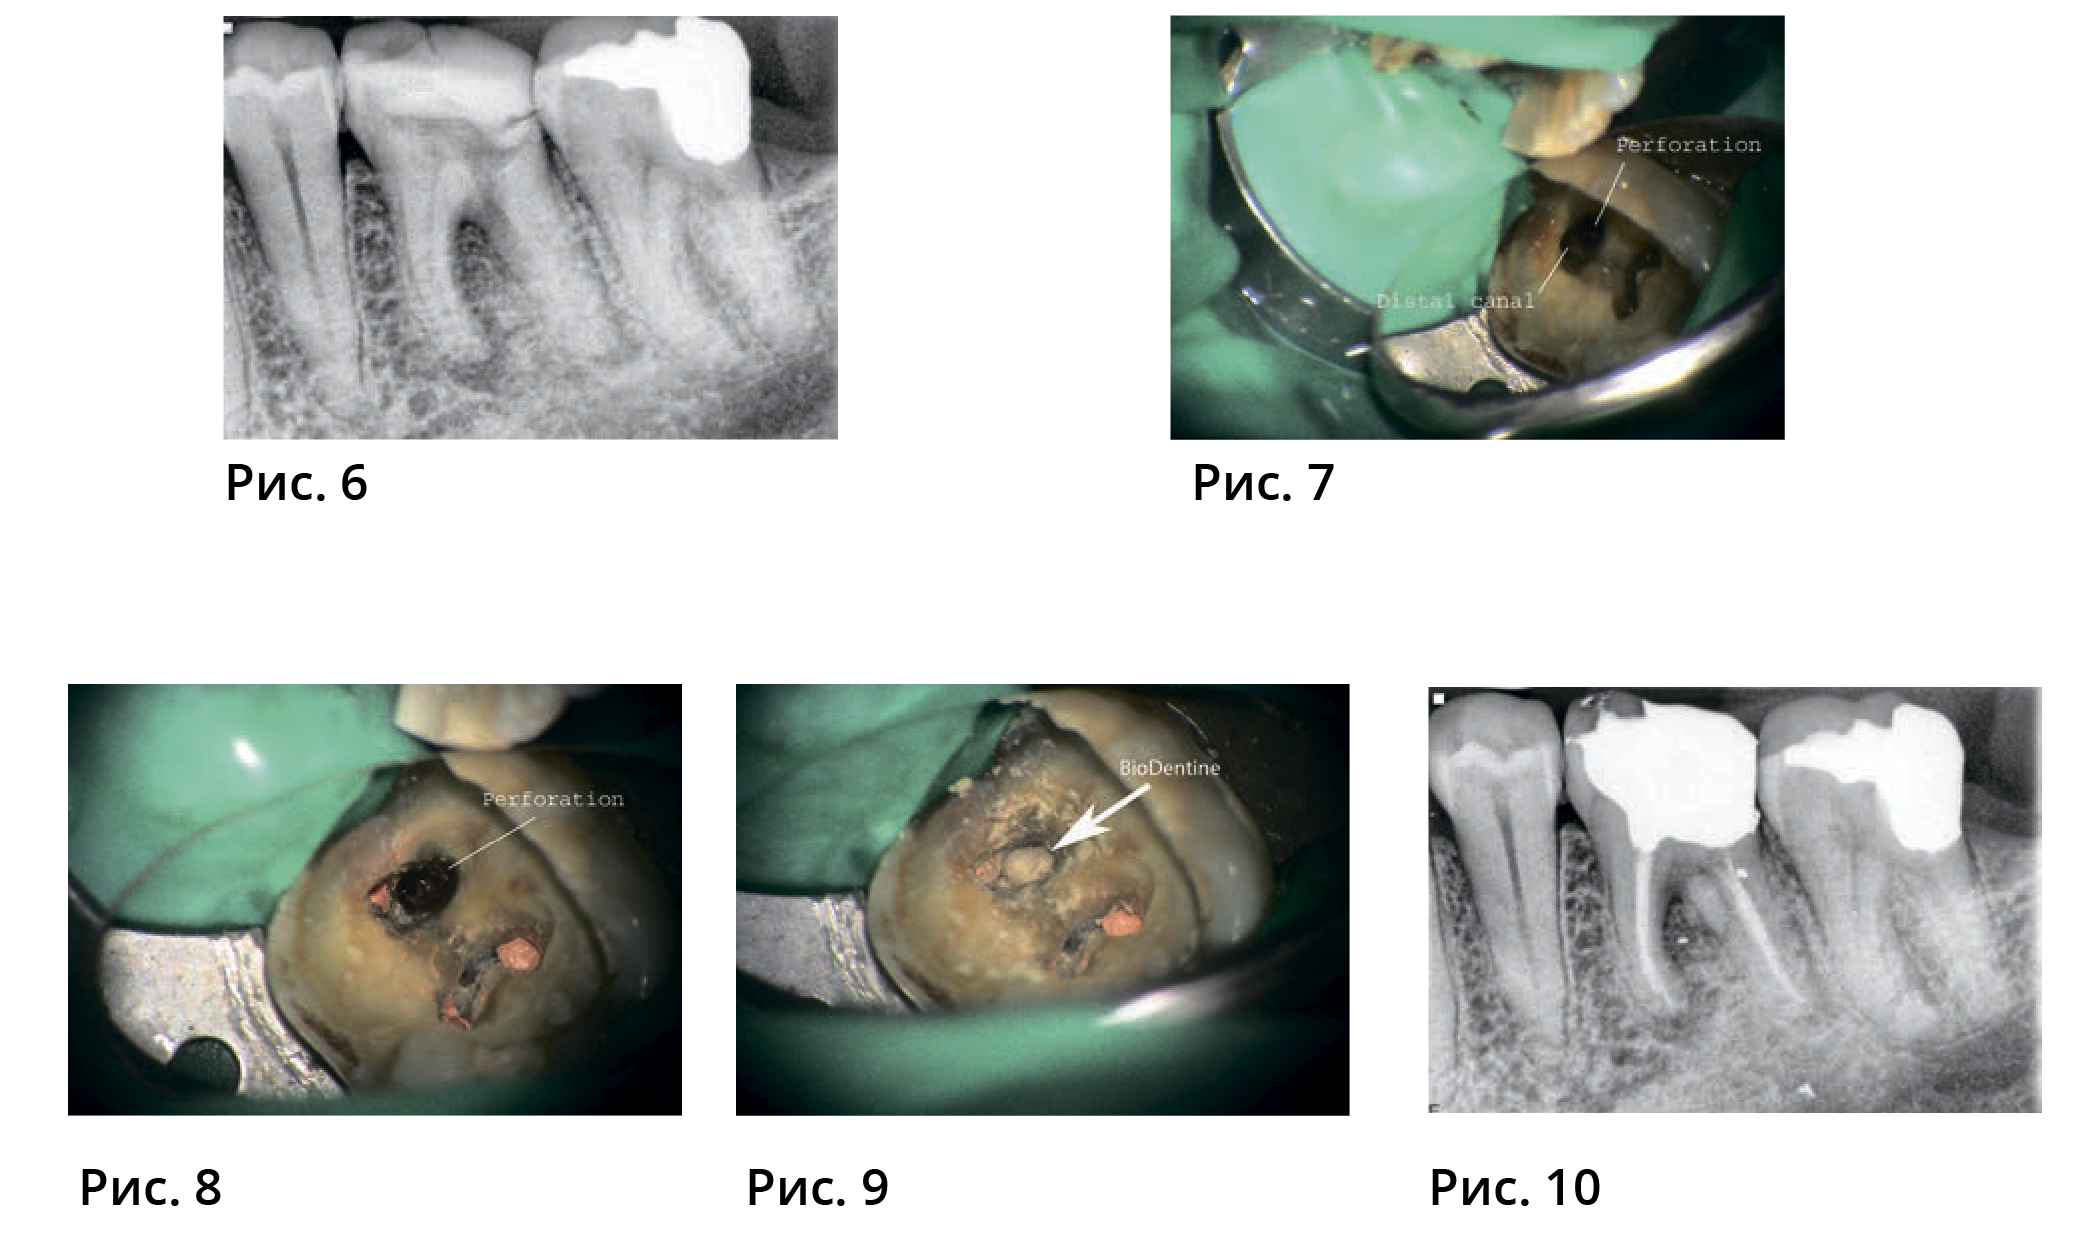

Случай № 2. 44-летний пациент, направленный стоматологом в связи с возможной необходимостью лечения корневых каналов зуба 36

Пациент сообщил, что лечивший его ранее стоматолог попытался выполнить лечение корневых каналов и заявил, что т.к. сделать это невозможно, зуб необходимо удалить. На зубе была установлена временная реставрационная конструкция, и наблюдались симптомы. На снимке, который сделали до лечения, наблюдался апикальный периодонтит и перфорация дна пульповой камеры. В процессе обследования перфорация дна пульповой камеры, ведущая в область фуркации с мезиальной стороны от дистальной стороны корня и дистальной стороны канала не была выявлена (рис. 6 и 7). Каналы обработали инструментами, очистили и запломбировали (рис. 8).

Перфорацию высушили бумажными штифтами крупного размера, затем в поврежденный участок ввели Biodentine и оставили его затвердевать на 12 минут (рис. 9 и 10). Так как процесс лечения предполагал фиксацию культи из амальгамы, во избежание смещения Biodentine поверх него нанесли СИЦ.На рентгенограмме, сделанной после лечения, можно рассмотреть устраненную перфорацию.

Через полгода пациент пройдет повторное обследование.